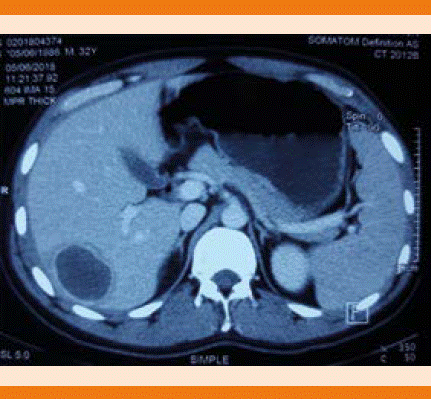

La tomografía de abdomen evidenció una lesión hipodensa localizada en el segmento VII del hígado, con tamaño de 3 x 3.4 cm, hallazgos compatibles con absceso hepático (Figura 2). Se realizó punción el absceso y se drenaron aproximadamente 20 mm3 de líquido purulento, además, se inició tratamiento antibiótico empírico con ceftriaxona y metronidazol, el cultivo del líquido purulento drenado no reportó crecimiento bacteriano.

Figura 2 Estudio tomográfico de abdomen; se evidencia lesión hipodensa en el segmento hepático VII, de 3 x 3.4 cm y densidad de 24 UH con realce periférico a la administración de contraste intravenoso.